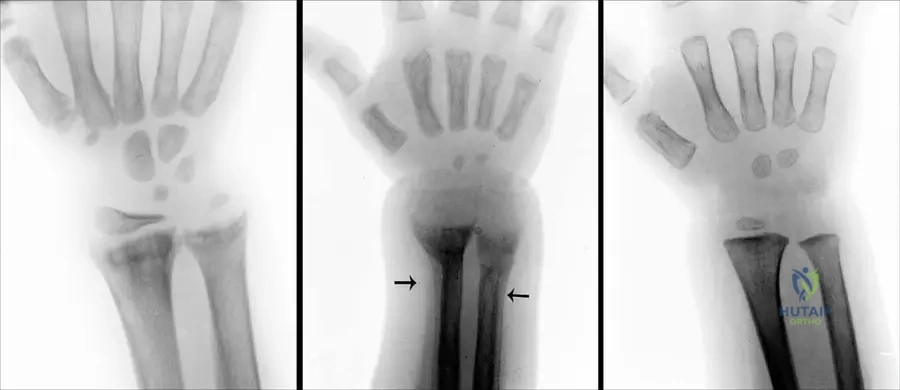

A 7-year-old boy presents with short stature, bowing of the forearms, and atypical clubfeet. Genetic testing is performed to confirm the diagnosis of Nievergelt type mesomelic dwarfism.

View Answer & Explanation

Correct Answer: C

Rationale: The text states that Nievergelt and Langer type mesomelic dwarfism is "caused by mutations in the SHOX gene." FGFR3 mutations are associated with achondroplasia, a common rhizomelic dwarfism, making it a plausible distractor for general dwarfism knowledge.

Question 35

A 6-year-old boy with a family history of mesomelic dwarfism presents with bilateral foot deformities. On examination, his feet appear rigid and malformed, consistent with atypical clubfeet. Radiographs are performed.

Correct Answer: D

Rationale: The text lists "atypical clubfeet" and "intertarsal synostosis" as features of Nievergelt and Langer type mesomelic dwarfism. Calcaneal-cuboid synostosis is a specific example of an intertarsal synostosis, but "intertarsal synostosis" is the broader, directly stated term in the provided text.

Question 41

A 7-year-old girl is diagnosed with mesomelic dwarfism, Nievergelt type, characterized by severe shortening of the forearms and lower legs, radio-ulnar synostosis, and atypical clubfeet. Genetic testing is recommended.

Rationale: The case text explicitly states that mesomelic dwarfism (Nievergelt and Langer Type) is "caused by mutations in the SHOX gene."

Main Distractor: A) FGFR3 - FGFR3 mutations are associated with achondroplasia and hypochondroplasia, which are different types of skeletal dysplasias, not mesomelic dwarfism.